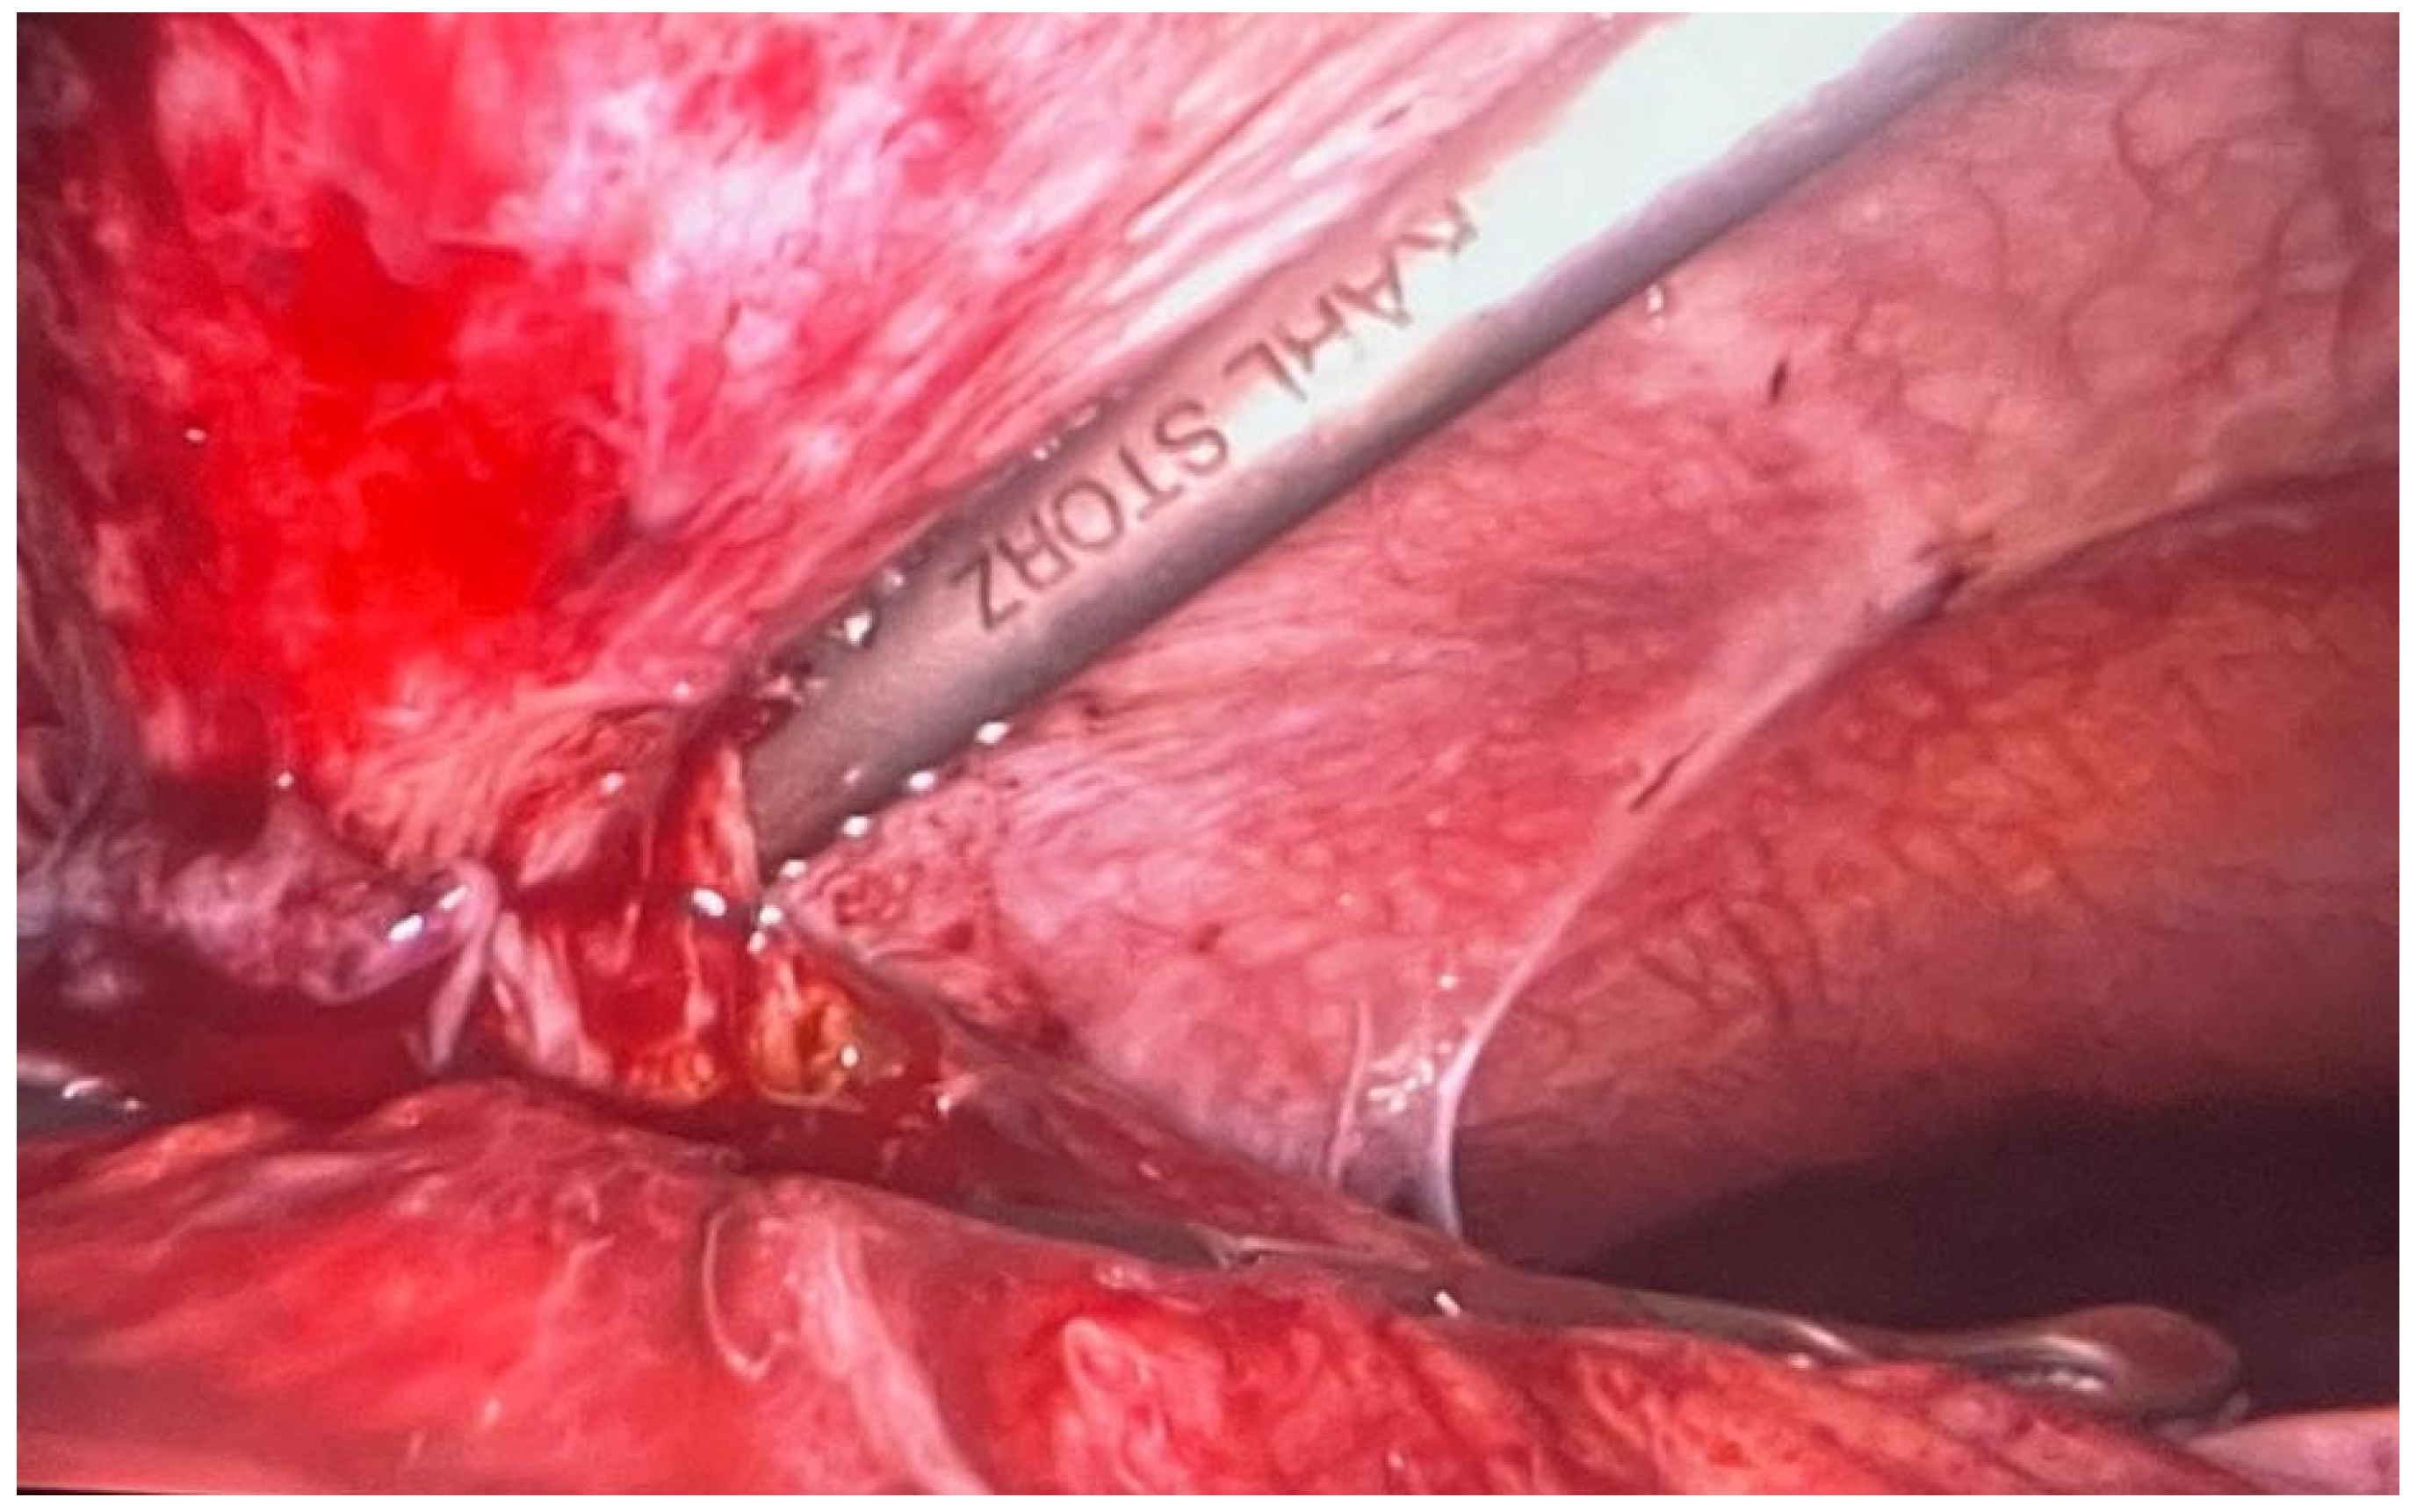

| Symptoms | Diagnostic | Surgical Intervention | Hemostatic Treatment | Evolution |

| Affected general condition and diffuse abdominal pain | Giant ruptured retroperitoneal with hemoperitoneum | Exploratory laparotomy with peritoneal lavage | Coagulation factor VIII and von Willebrand Factor | Favorable |